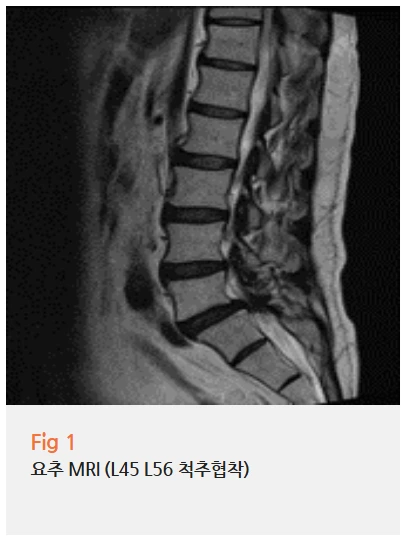

환자분께 허리 MRI 검사를 권해드렸어요.

결과를 보는 순간 '역시' 하는 생각이 들더라고요.

요추 4-5번, 5번-천추 1번 사이에

중등도 이상의 척추관협착증이 보였고,

신경근이 상당히 압박받고 있는 상태였어요.